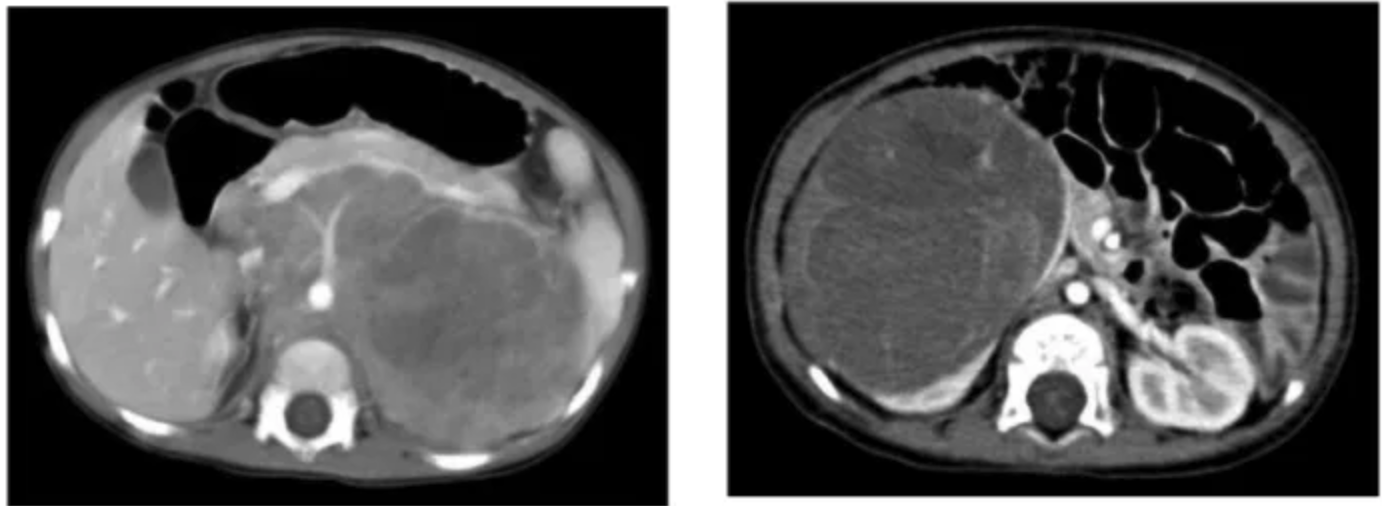

좌: wilm’s tumor in left kidney, enhancing renal tissue의 displacement (화살표)

abdominal vessel을 encase하지 않고 midline crossing을 보이지 않음.

우: bilateral wilms tumor

신경모세포종 vs 윌름 종양

• Neuroblastoma: midline crossing, major vessel encasement, calcification 동반

• nephroblastoma: midline 침범 x, vessel encasement x (밀어냄)